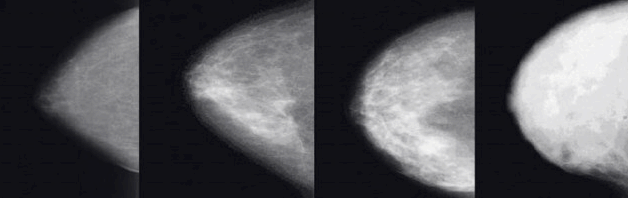

3D 유방촬영술(DBT)

디지털 유방단층촬영술(Digital Breast Tomosynthesis, DBT)은 기존 2D 유방촬영술의 한계를 보완한 최신 기술입니다. 여러 각도에서 유방을 촬영하여 3차원 영상을 구성함으로써 조직의 중첩을 줄이고 병변을 더 명확하게 볼 수 있게 합니다.

3D 유방촬영술은 2D 촬영보다 진단 정확도가 높아 치밀유방에서도 미세석회화 등 작은 병변까지 확인할 수 있습니다. 연구에 따르면 3D 유방촬영술은 치밀유방에서 유방암 발견율을 약 27% 증가시키고, 위양성률을 15% 감소시키는 효과가 있습니다. 최근 국내 주요 의료기관에서도 도입이 확대되고 있습니다.